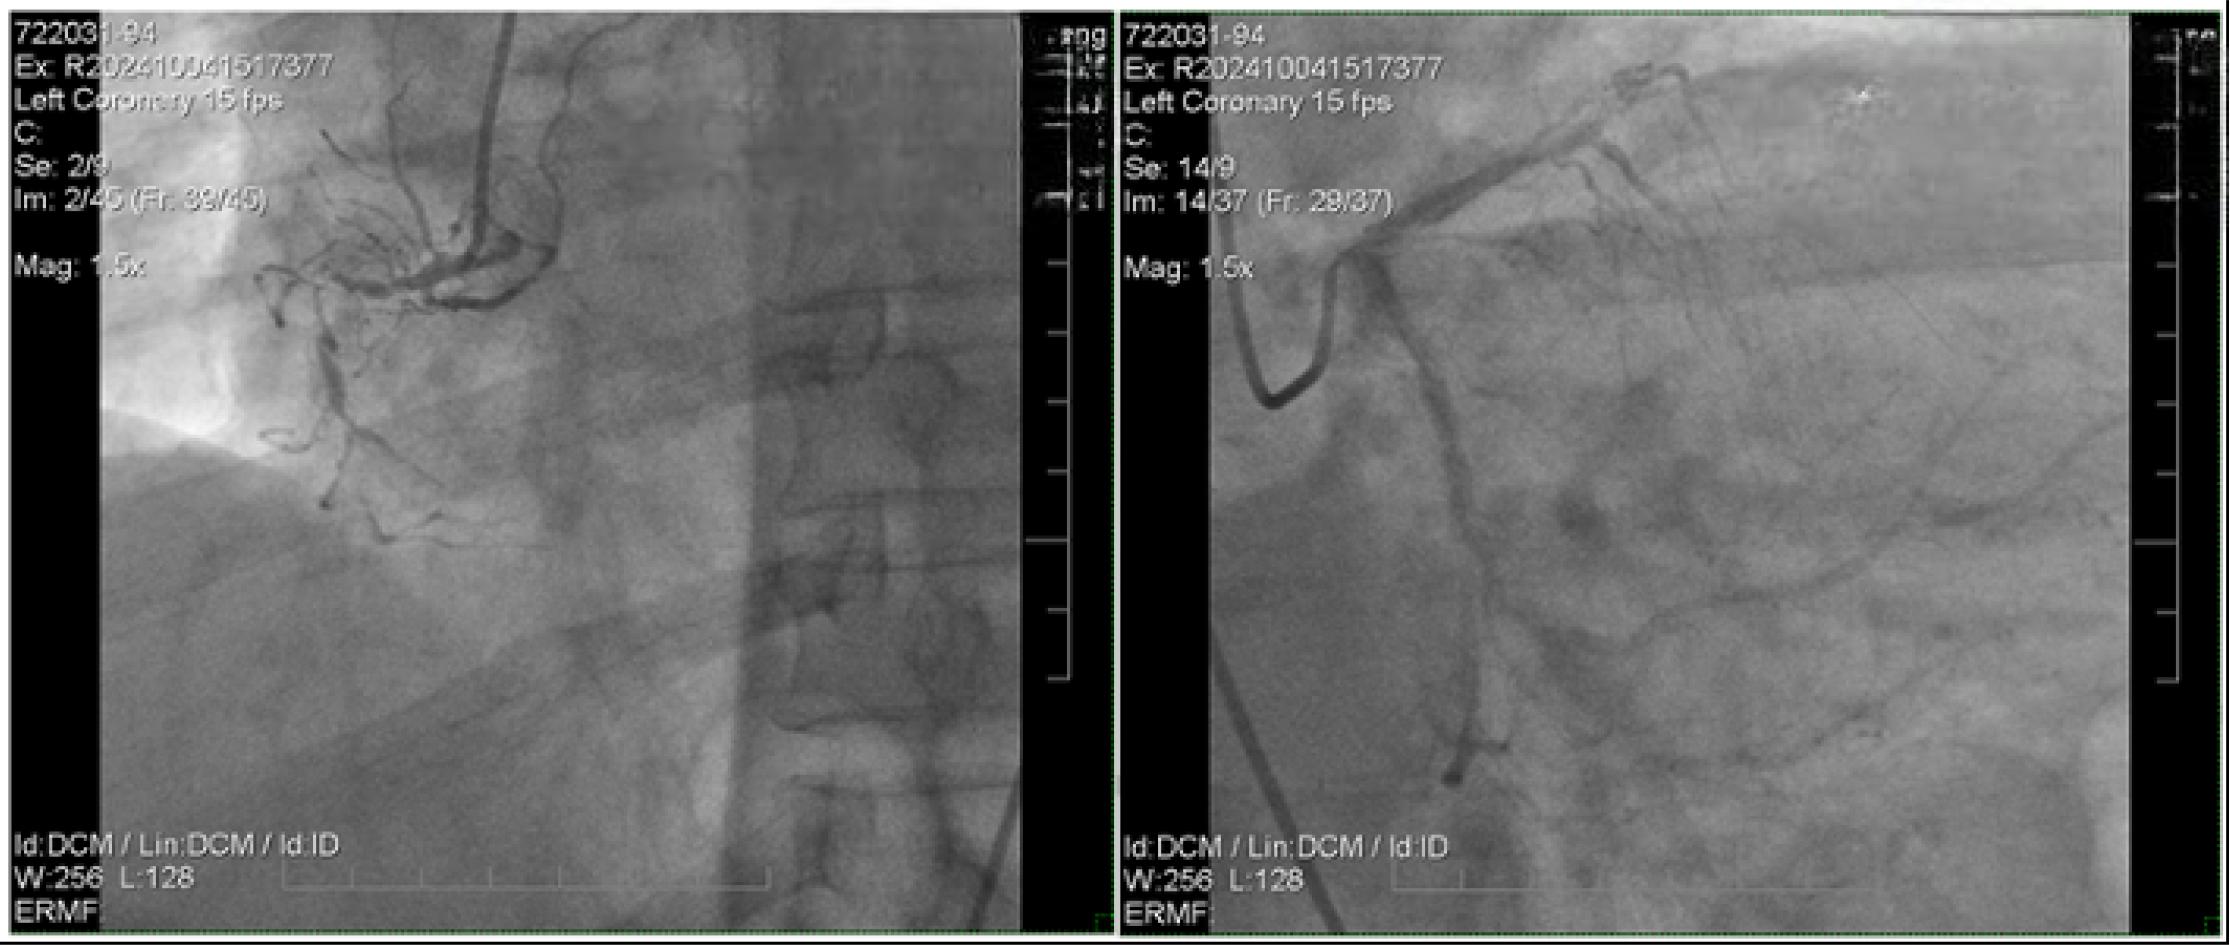

Coronary angiogram revealed stenosis of the left main coronary artery at the ostium and diffuse significant stenosis involving the left anterior descending artery, left circumflex artery, and right coronary artery with total occlusion at distal part supplied by collateral from LAD, indicative of left main and triple vessel disease (Figure 2). The patient was advised to undergo coronary artery bypass grafting (CABG). However, both the patient and his family declined further invasive treatment, citing his underlying comorbidities. Coronary angiogram was performed with the administration of a total of 40 mL of iodixanol (Figure 2).

Coronary angiogram